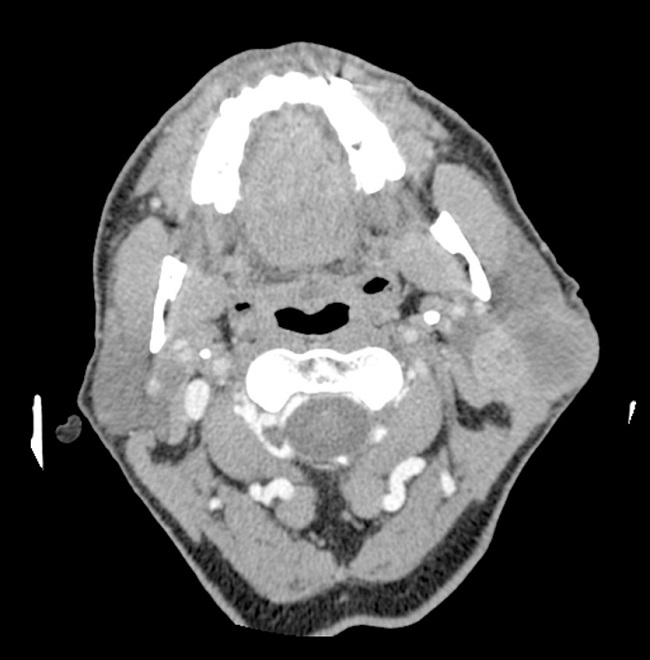

A CT scan revealed a 57 mm × 40 mm × 27 mm heterogeneously enhanced left parotid mass, involving both lobes of the gland (Fig. 2). There was no evidence of osteolytic changes in mandibular bones. Moreover, no invasions of the masseter muscle or of the parapharyngeal space were showed. A few 15-19 mm lymph nodes in the retro- and submandibular space were described. Fine needle aspiration biopsy confirmed pleomorphic adenoma. The patient underwent surgical treatment involving left subtotal parotidectomy. En bloc removal of the tumor was achieved with the excision of the superficial lobe. The facial nerve was preserved. Macroscopically, the mass was enveloped, solid and yellowish, with one cyst (1.5 cm in diameter) on the marginal part. Microscopically, the tumor mass included three different morphological patterns (Fig. 3). Pleomorphic adenoma was the dominant component. Within its tissue atypical cells of carcinoma ex pleomorphic adenoma were found. The marginal part of the solid mass included Warthin tumor cells. Surgical margins were free from neoplasm.